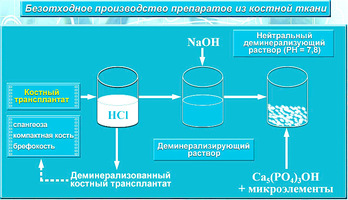

4. Схема деминерализации материала для получения ДМ-форм